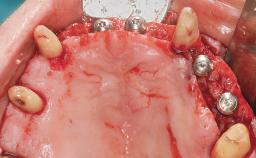

Conventional Loading of Eight Implants in the Maxilla and Final Restoration with a Full-Arch Gold-Ceramic FDP

A 35-year-old Caucasian female presenting with advanced periodontal disease involving both the maxillary and the mandibular dentition was referred for evaluation. The patient, a non-smoker in good general health, requested treatment for recurrent periodontal abscesses, tooth mobility, and discomfort during chewing, as well as restoration of her missing teeth with a fixed prosthesis to improve mastication and esthetics. All residual maxillary teeth exhibited plaque deposits, deep pockets, bleeding on probing, and class III mobility and were evaluated as hopeless. All residual mandibular teeth except tooth 37 could be maintained after periodontal therapy.

# of Implants 8

Type of Implants One-Piece

Bone Augmentation Horizontal|Staged|Vertical

Augmentation Materials Autogenous block(s)